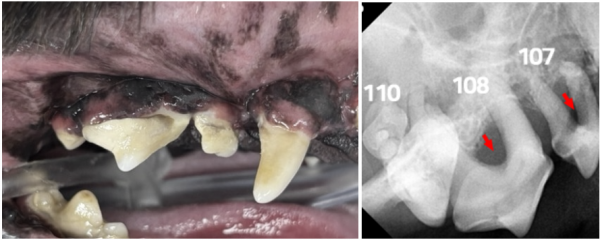

de70cef8385ff32e9ecfc65bf523daeb_1766380431_8105.png

우측 어금니에서는 육안으로

치주염과 치조골 소실이 뚜렷하게 보였습니다.

방사선상 107·108·110번 치아는

· 치조골 50% 이상 소실

· furcation involvement(화살표) Class 3 이상

이 경우 강아지 치아 보존이 매우 어렵기 때문에 발치 후

봉합이 가장 안전한 선택이었습니다.